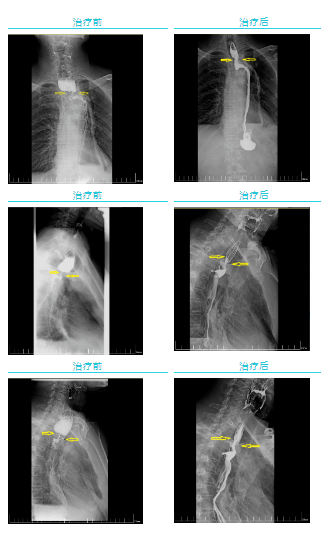

經(jīng)過(guò)一個(gè)周期的放療,李先生明顯感受好多了,可以正常吃飯喝水。食管鋇餐造影顯示,食管吻合口區(qū)腫塊明顯縮小,食管狹窄減輕。